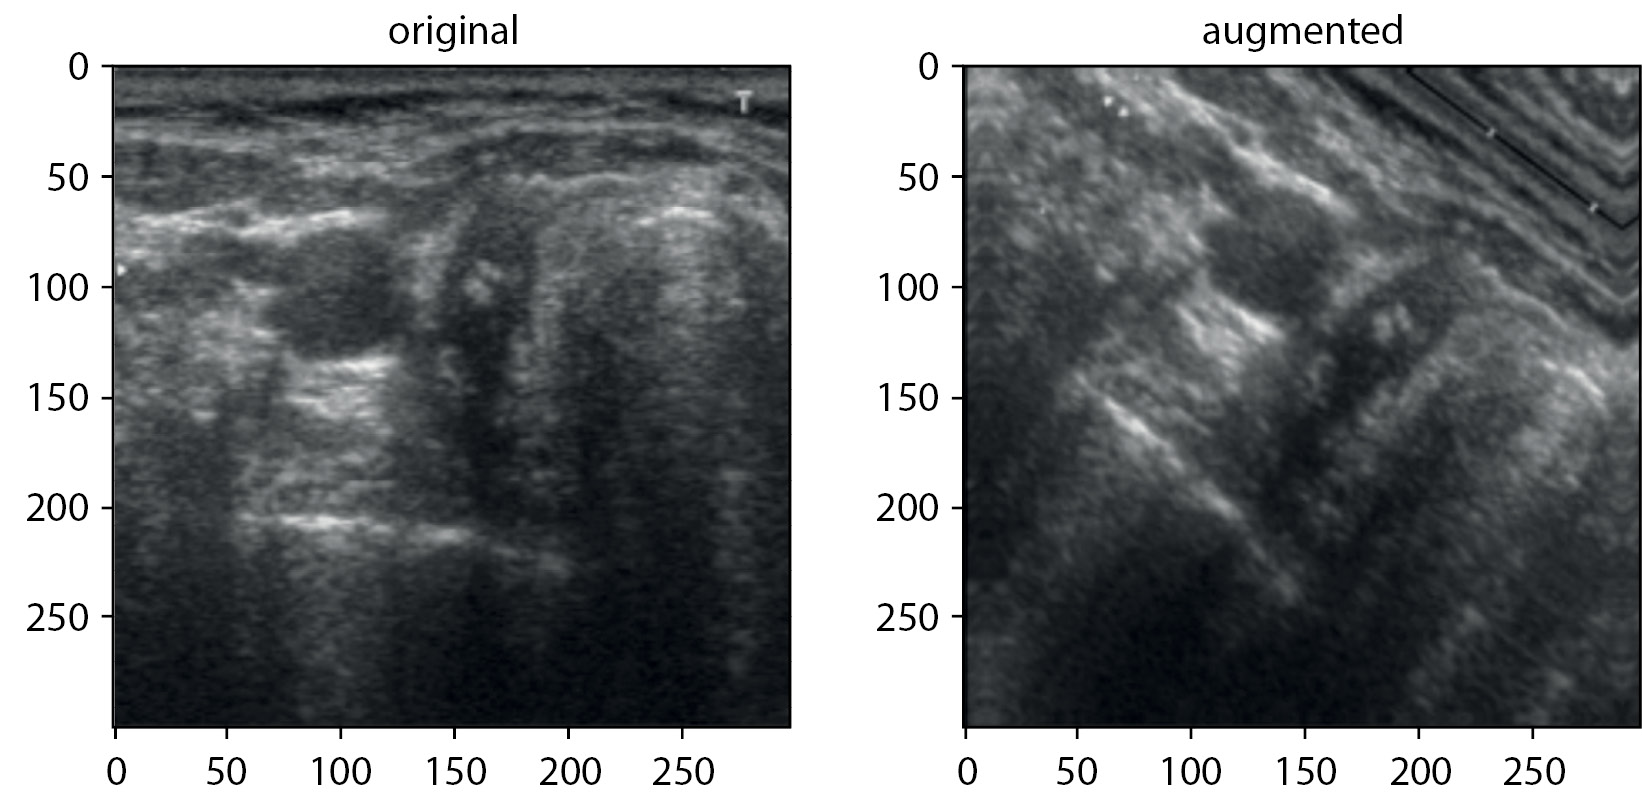

6. Риc. 6. Оригинальное и аугментированное ультразвуковое изображение | |